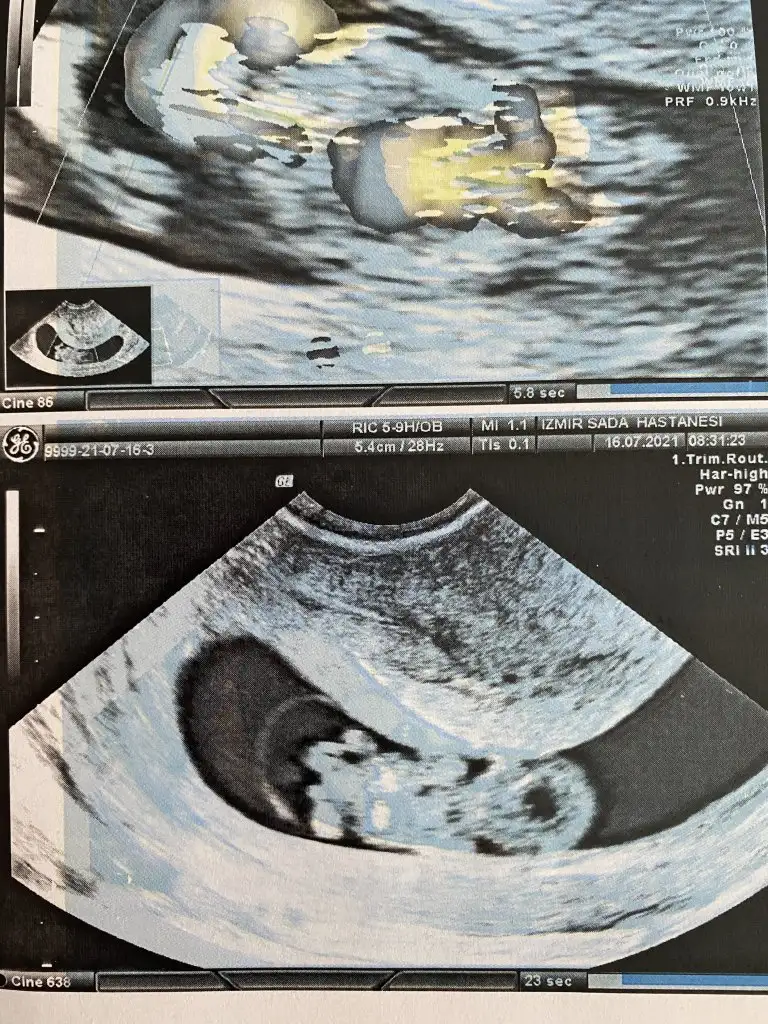

Kız görünüyorMerhabalar bunu da bakarmısınız![]()

En iyi 11 12 13 haftalar olmalıIkra meyra merhaba 9+5 bugün çekildik bi tahminin var mı cnm ?

Erkek gibiBuda benim yorumlayabilirmisin![]()